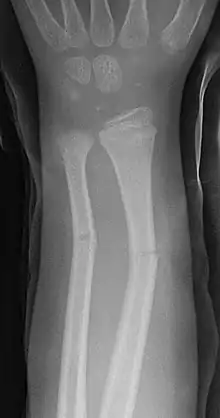

Radiografía de una fractura en tallo verde, que afecta a los huesos cúbito y radio, en el antebrazo de un niño.

Las fracturas en tallo verde afectan por lo general a la porción central o diáfisis de los huesos largos de los niños, sobre todo a la región del antebrazo, muñeca y clavícula. Raramente se produce en otros huesos como la tibia y el fémur. Cuando afecta al antebrazo puede existir fractura del cúbito, el radio o ambos huesos simultáneamente.